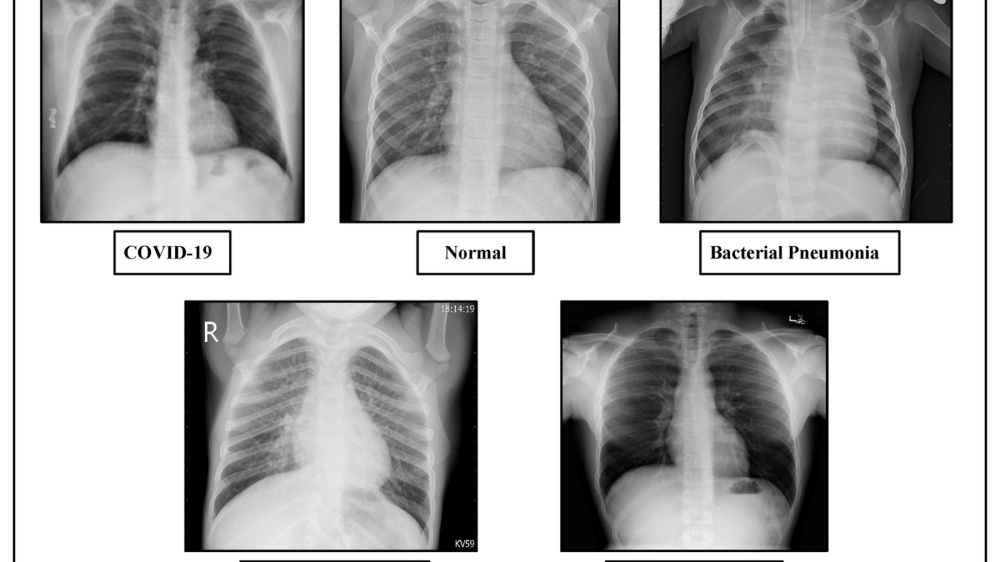

So sánh triệu chứng viêm phổi ở người lớn và trẻ em

Dấu hiệu viêm phổi ở trẻ sơ sinh và trẻ nhỏ